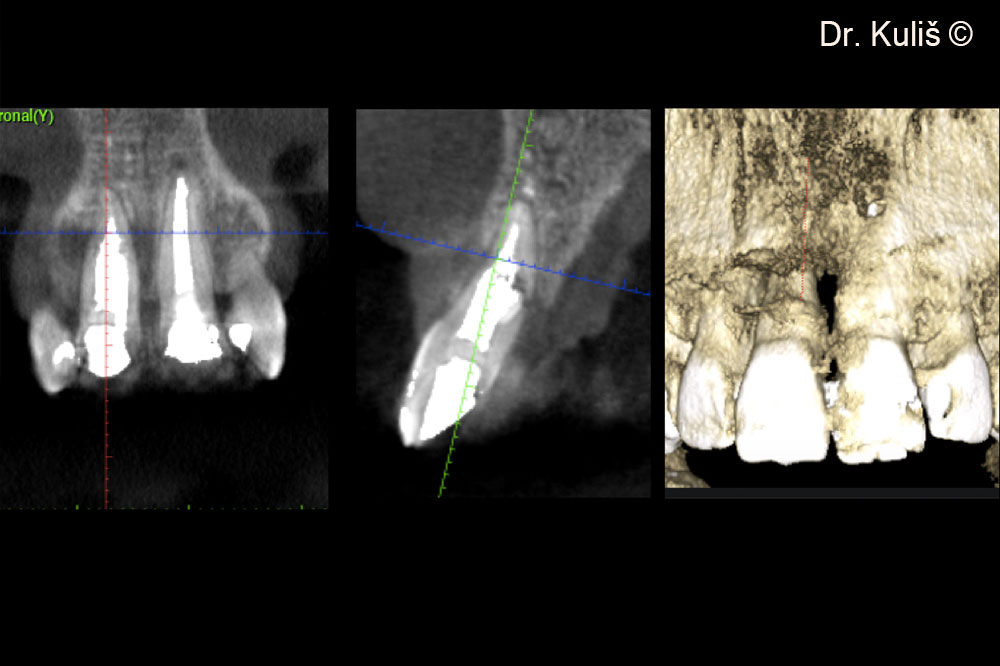

Hình ảnh chụp CBCT ban đầu cho thấy khuyết tật xương má với sự thiếu hụt hoàn toàn xương má.

Vị trí cấy ghép có đường kính 3,75mm.